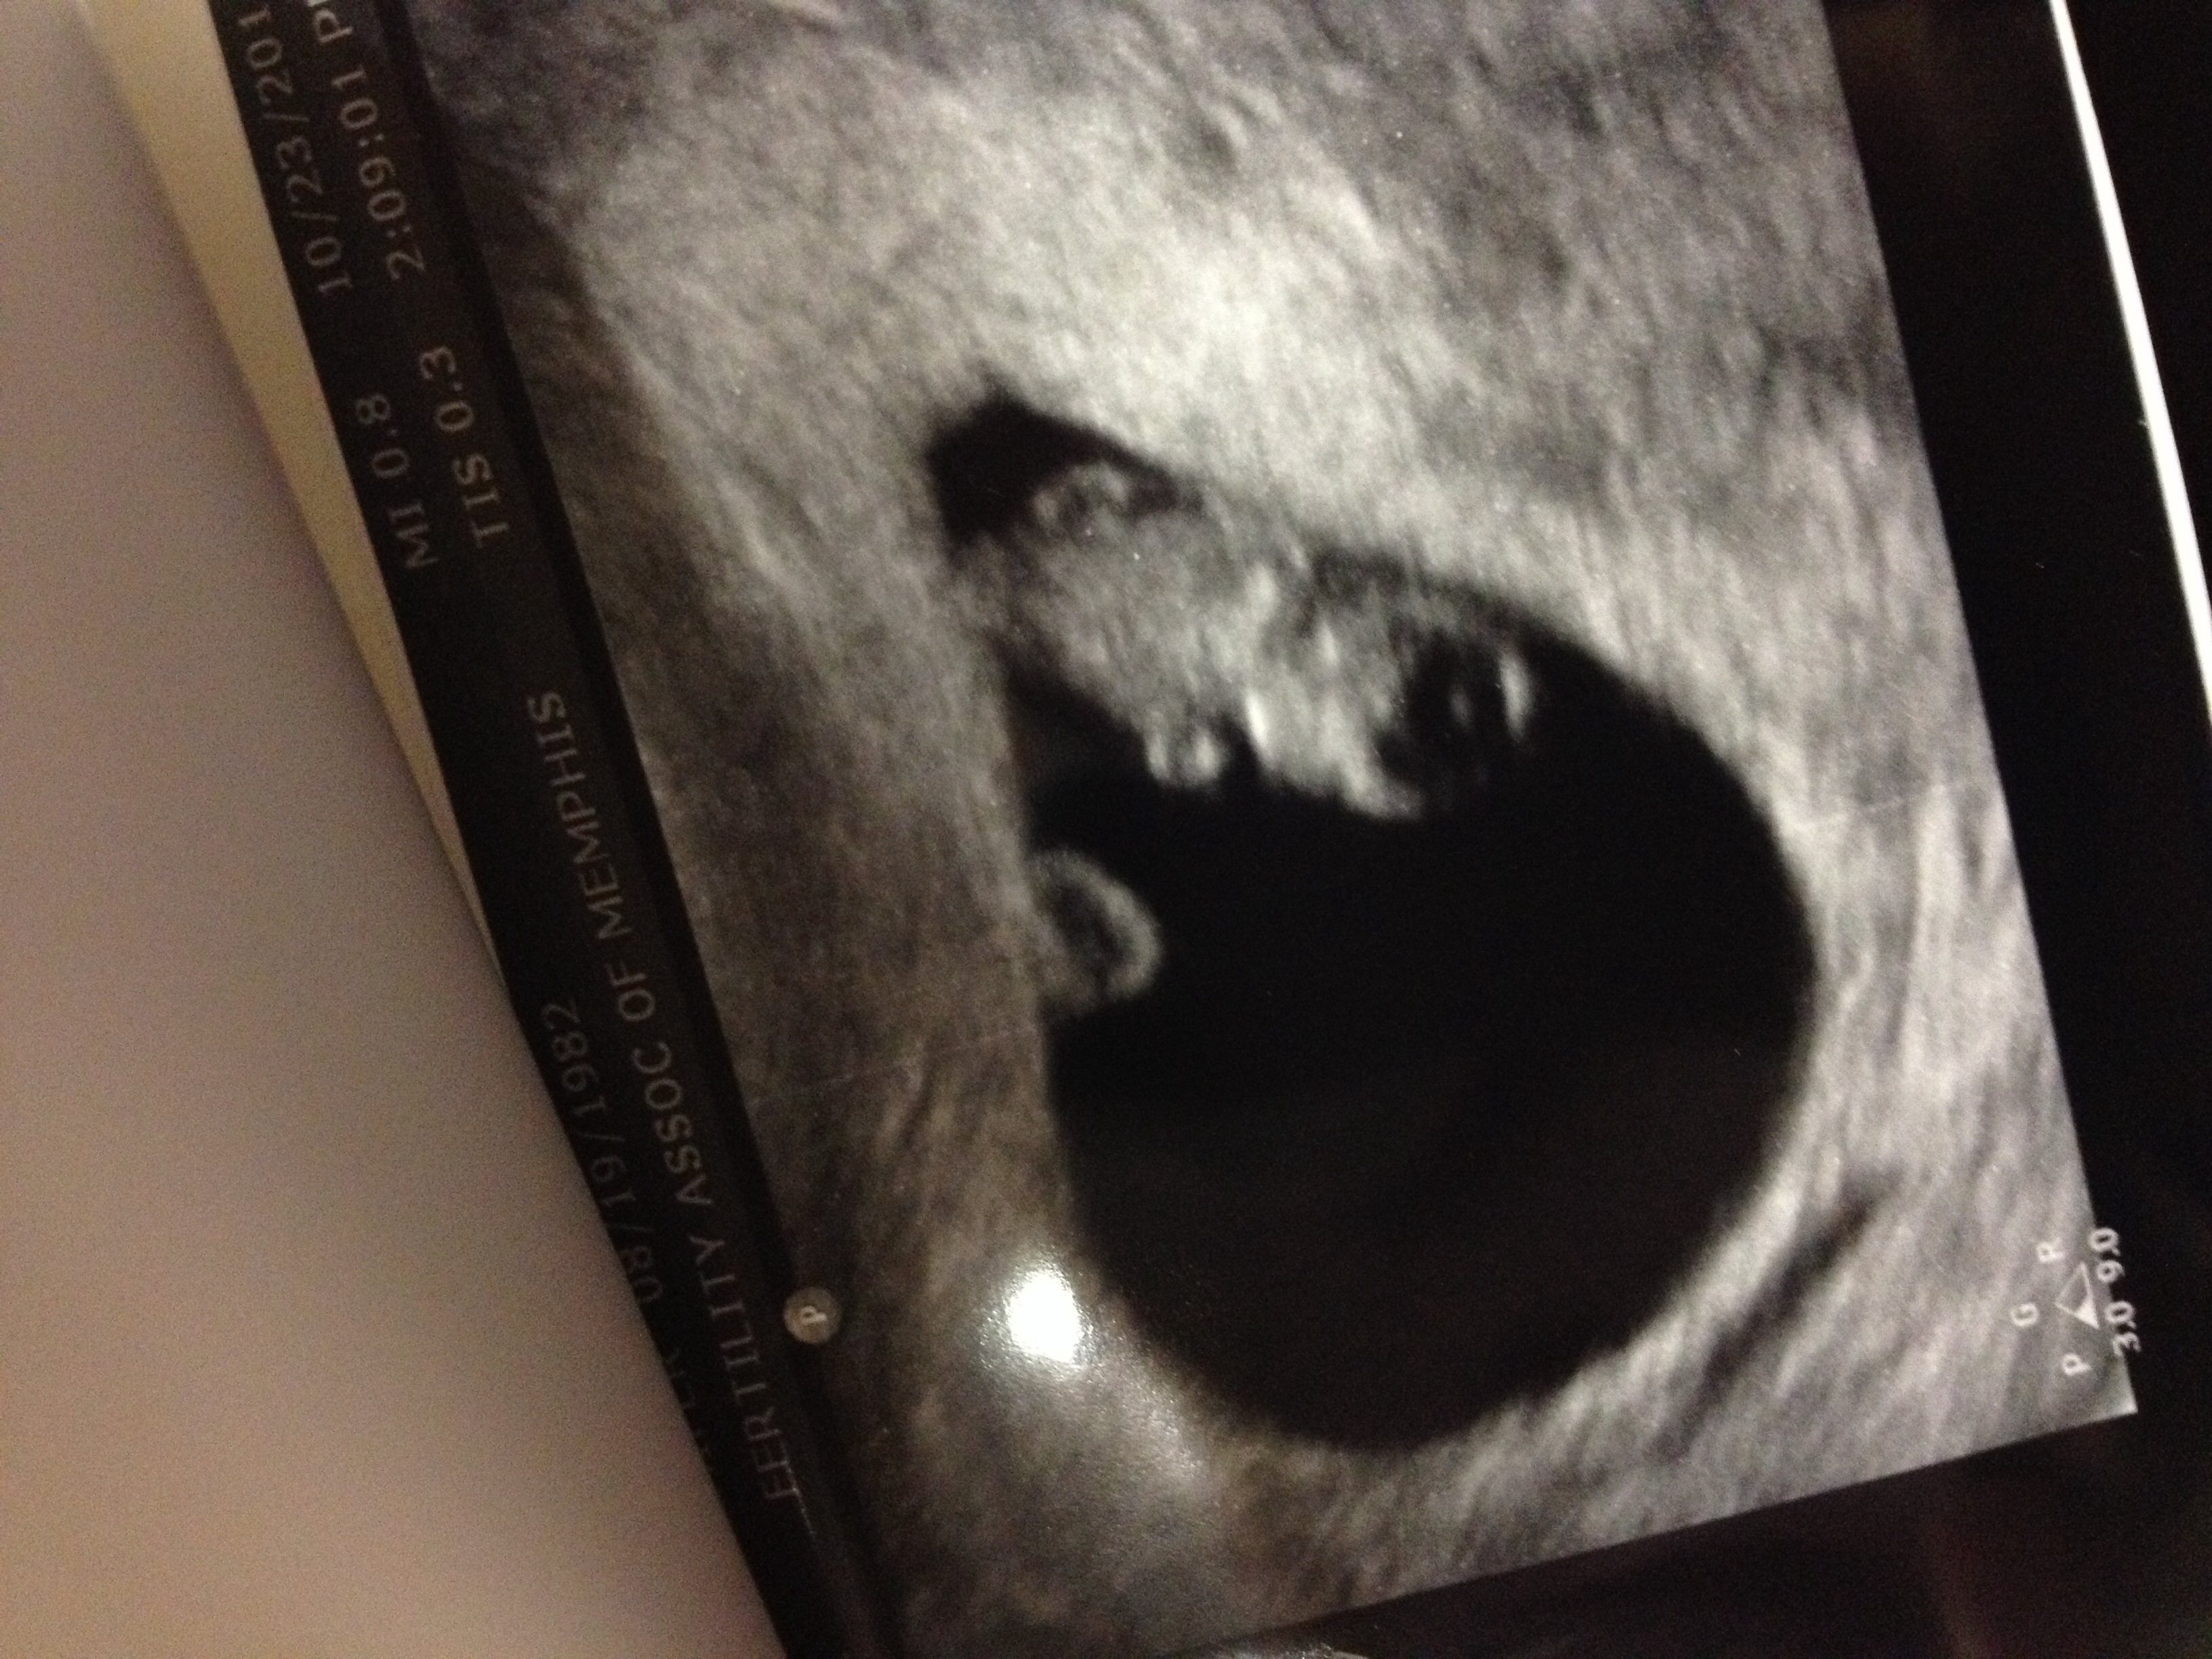

• Mine is an IVF pregnancy, so they monitor closely early on. First ultrasound was at 6w5d; we saw the yolk sac and fetal pole with a heartbeat of 127 bpm. It was such a relief to hear that everything was measuring on track! 2nd ultrasound was yesterday at 8w1d and I was measuring 1 day ahead. It's really starting to look like a baby now, with a head, body, and nubby arms and legs; it was incredible to see! Heartbeat was at 168 bpm, and we saw where the brain is developing, even got to see the umbilical cord. One more ultrasound with my RE at 10w5d before he releases me to the OB.